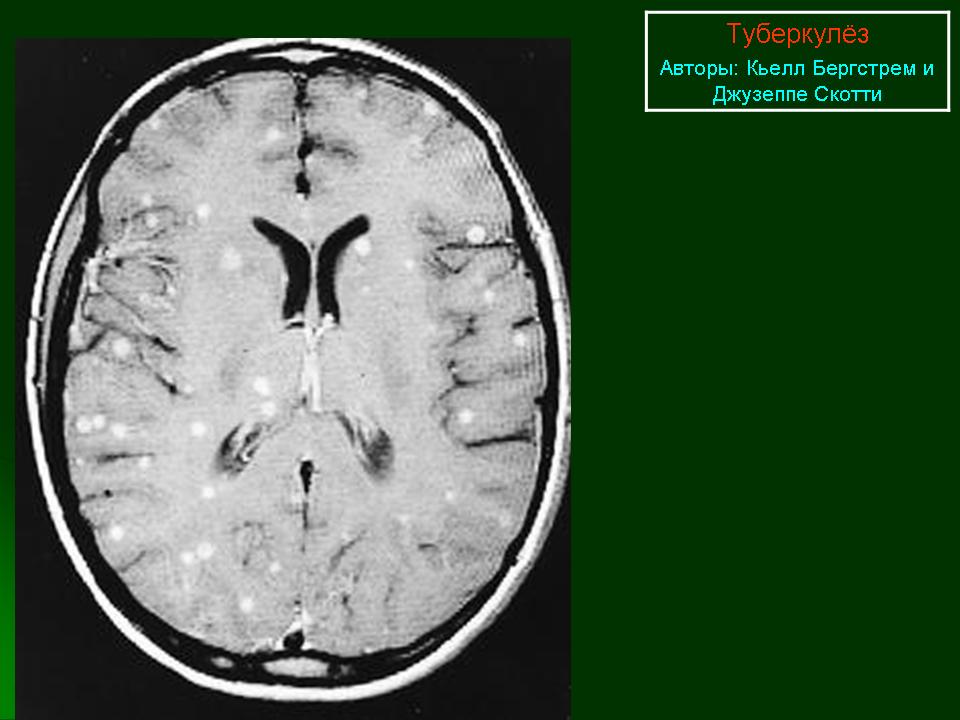

Туберкулёмы.